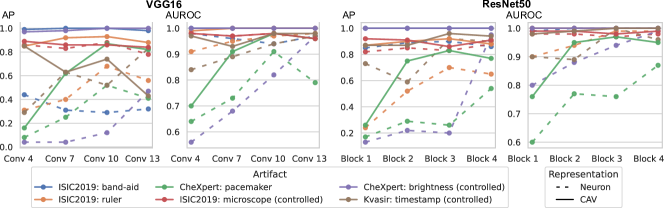

6.3 Biased Sample Retrieval

In this section, we leverage latent bias representations, either via directions or individual neurons, to retrieve biased samples and measure how well bias samples are separated from clean samples. We compute bias scores as defined in Eq. 1 by projecting latent activations onto the bias direction. As we are mostly interested in the ranking capabilities, i.e., artifact samples should be assigned higher bias scores than clean samples, we measure Area Under the Receiver Operating Curve (AUROC) and Average Precision (AP), considering both real and controlled artifacts. For real artifacts, we evaluate retrieval using existing artifact labels, while we have ground truth information for controlled experiments. We train CAVs using Support Vector Machines (SVMs) on different layers of VGG16 and ResNet50 models for all datasets, reporting AUROC and AP on unseen test samples. Note, that while Pahde et al. [58] claim that classifier-based CAV computation can yield imprecise concept directions, they argue that SVM-CAVs are superior for predicting concept presence, the main goal of this experiment. In Fig. 7, we show the results for different layers of VGG16 and ResNet50 using single neurons (dashed line) and CAVs (solid line) as bias representation. Best neurons are selected using the validation set. The results indicate that CAVs generally outperform single neuron representations for sample retrieval, and the layer choice is crucial depending on the bias type. For instance, while CAVs for layers closer to the model heads can detect pacemaker samples, they fail for earlier layers.